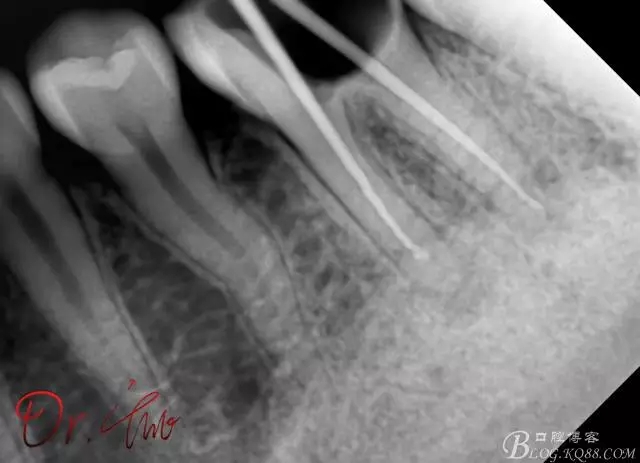

試主尖,近中頰側(cè)形成臺階

640.webp (7).jpg

試主尖,近中頰側(cè)再次拍片查看臺階位置及確定長度

640.webp (8).jpg

試主尖,近中頰側(cè)試主尖,此時手用銼02錐度的已擴到30號,可以明顯感覺到臺階位置,挫預彎后找好正確位置可順利到達根尖,但是機用銼就是下不去,也是郁悶